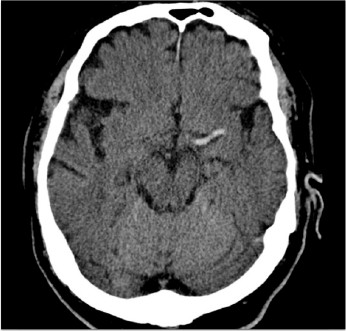

Uma mulher de 65 anos, em pós-operatório de bypass coronariano, desenvolveu hemiparesia direita e dificuldade de expressão ao despertar da anestesia as 15:00 hs. Ela não apresentava nenhum déficit neurológico até 12:00 hs.

Uma TAC de crânio foi feita imediatamente:

As 16 hs, a equipe teve que tomar uma decisão terapeutica: Qual das opções abaixo ofereceria a melhor chance de recuperação funcional neurológica para a paciente: